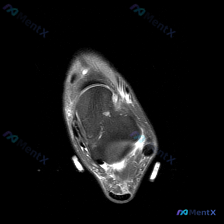

最近看到一个挺有讨论价值的读片病例,整理了整个分析思路分享给大家。 病例背景 本次分析对象为踝关节MRI-T2序列-轴位单一扫描层面,患者主诉怀疑存在软组织积液,要求对影像进行评估。 --- 影像核心信息整理 先给大家整理一下这张影像的关键发现: 1. 解剖结构层面:该层面位于踝关节上方,可显示胫骨...